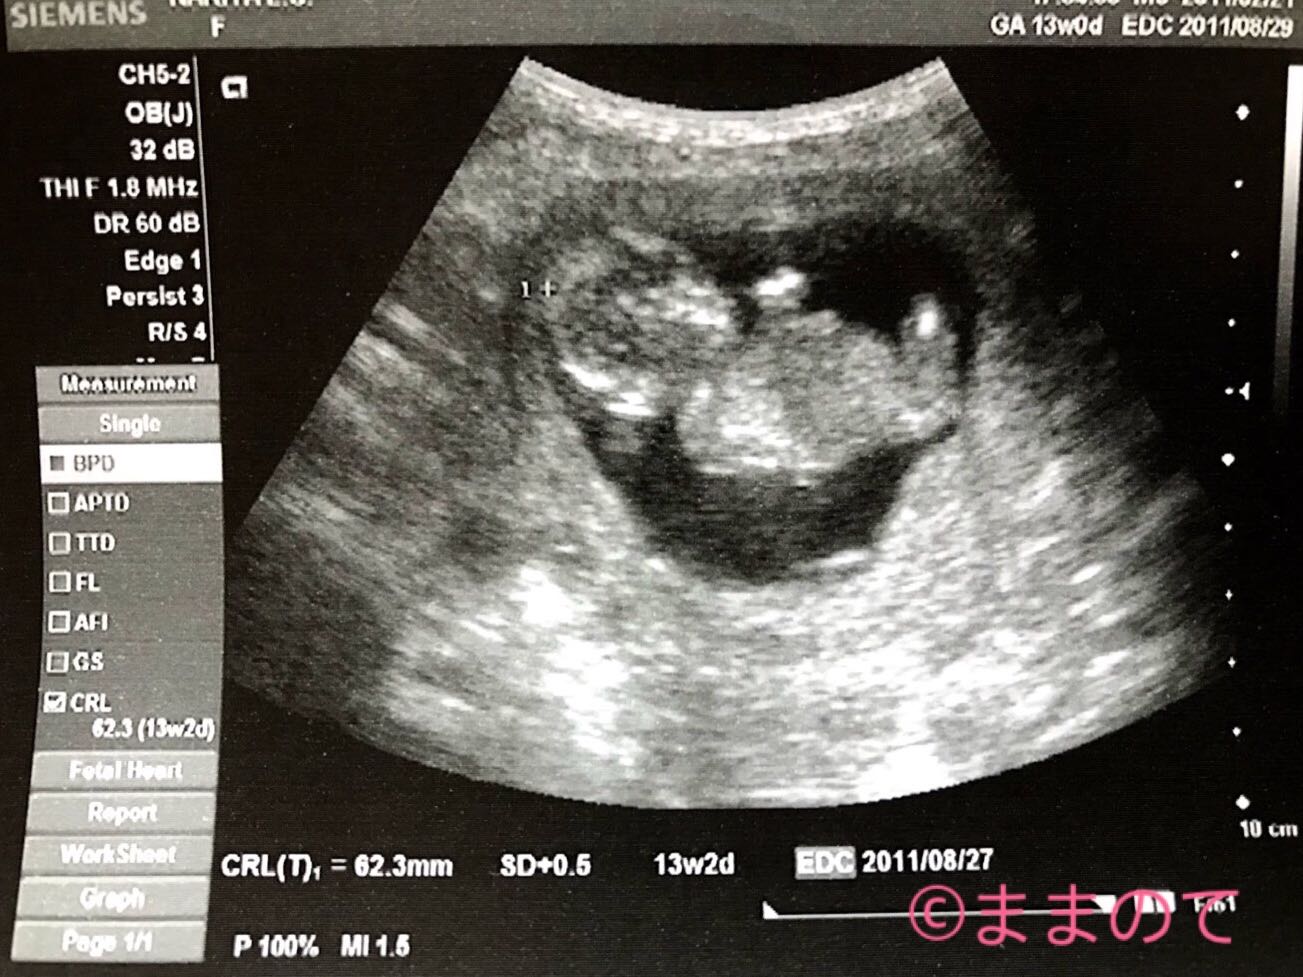

妊娠13週の赤ちゃんのエコー画像

GA(妊娠週数)は13週0日、SD(標準偏差)が13週2日の腹部エコー画像です。頭部と手足がしっかりと写し出され、人間らしい姿となってきています。横からの角度で表情はわかりませんが、丸い頭部は思わずなでてあげたくなるかわいさです。